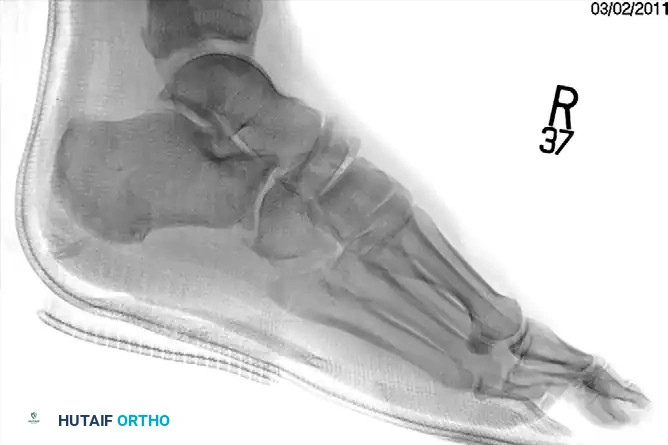

Clinical Evaluation and Radiographic Parameters

Any injury resulting in midfoot tenderness, swelling, or an inability to bear weight merits rigorous evaluation.

Radiographic Evaluation:

Standard non-weight-bearing radiographs often miss subtle instability. Weight-bearing radiographs are absolute requirements if the patient can tolerate them. If the patient cannot bear weight, a short-leg cast should be applied for 10-14 days, followed by repeat weight-bearing films.

Key radiographic parameters to evaluate:

1. The medial shaft of the 2nd metatarsal must align perfectly with the medial aspect of the middle cuneiform on the AP view.

2. The medial shaft of the 4th metatarsal must align perfectly with the medial aspect of the cuboid on the oblique view.

3. The 1st metatarsal-cuneiform articulation must show no incongruency.

4. The "Fleck Sign": Look for a small bony avulsion in the space between the medial cuneiform and the base of the 2nd metatarsal. This represents a bony avulsion of the Lisfranc ligament.

5. Evaluate the naviculocuneiform articulation for subtle subluxation.

If plain radiographs are equivocal but clinical suspicion remains high, CT imaging is excellent for identifying occult fractures, while MRI is the gold standard for evaluating the integrity of the Lisfranc ligament complex.